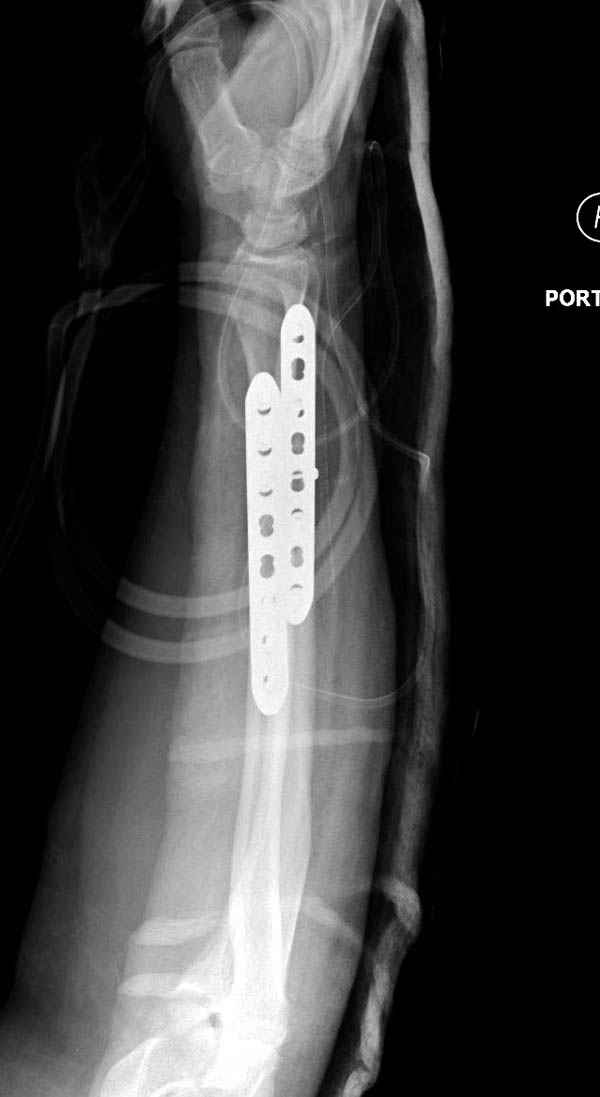

Второй случай, для лечения перелома проксимального

плеча применили пластину "Hand Innovation"

http://www.handinnovations.com/pdf/S3_technique.pdf

Пластина имеет преимущества перед другими "Locking

Implants", потому что пластину можно уложить намного ниже чем другие пластины и имеется возможности проведения шурупов под 130 градусным углом, таким образом можно уменьшить операционный разрез в проксимальной части.

Прооперирован вчера на 13 день после поступления.

Больному 41 и из-за гемодинамической нестабильности в течение первых 7 дней был в реанимации под интубационной седацией.

Кроме перелома плеча у больного старый дистракционный перелом T12-L1 оперированный когда-то и кем-то, открытый перелом костей предплечья, который был прооперирован в ночь поступления, после I&D (хирургической обработки). Из-за разрыва селезенки при поступлении травма хирургами произведено удаление.